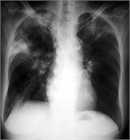

1. Q熱コクシエラ肺炎症例の胸部X線所見は典型例では多発性の肺野斑状影を呈する。